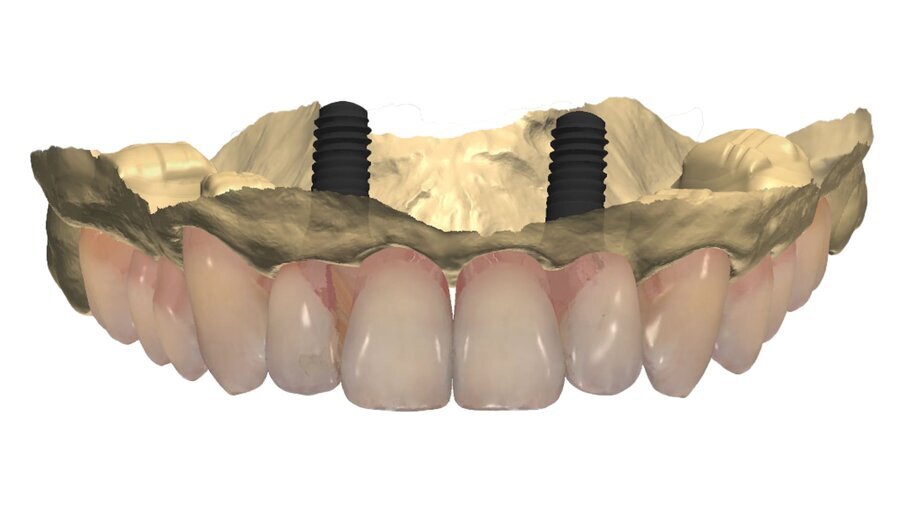

L’informazione diagnostica dettagliata è fornita dalla CBCT, pertanto abbiamo pianificato la sua esecuzione dopo la prima provvisorizzazione dell’arcata superiore evitando lo scattering da metalli presenti. Il file STL del wax-up (Fig. 6) associato al file STL dell’impronta senza provvisorio (Fig. 7) e al file DICOM radiologico (Figg. 8, 9) ha permesso una corretta progettazione chirurgico implantare (Fig. 10) nel rispetto della porzione ossea della cresta residua, ottimizzando la conseguente realizzazione della dima chirurgica (Fig. 11) per il posizionamento degli impianti in sede 1.2 e 2.2 (Figg. 12-14) anche nel rispetto della posizione degli elementi in antagonismo (Fig. 15). Il primo provvisorio avrà diverse funzioni tra cui la valutazione dell’inclinazione coronale, l’ingombro volumetrico e il supporto labiale del gruppo frontale per la correzione dell’emergenza del labbro superiore (Fig. 16). Dopo un breve periodo di stabilizzazione funzionale di almeno due mesi, si valutano i movimenti mandibolari, masticatori, il ripristino dei tessuti parodontali e il condizionamento biologico degli elementi intermedi. Nello specifico del caso trattato abbiamo evidenziato subito un collasso della masticazione associato a un morso profondo che non avrebbe consentito alcuna protesizzazione degli elementi mancanti (Fig. 2). Pertanto abbiamo dovuto realizzare un rialzo di masticazione anche per correggere l’emergenza degli elementi sostitutivi. La preparazione degli elementi residui concepita ha eliminato tutti i materiali che avrebbero creato un disturbo nell’indagine radiologica (Fig. 17).

Fig. 14_Visione palatale del wax-up completo in marrone, sovrapposto alla visione ossea in azzurro con gli elementi sottostanti in viola. L’impianto in posizione 1.5 anche se progettato non è stato inserito preferendo un progetto protesico convenzionale con il collegamento a ponte degli elementi limitrofi.

Fig. 15_Nella visione di centrica è possibile valorizzare il progetto di posizionamento che ha tenuto conto della disponibilità ossea per sfruttare al massimo l’osso nativo, la posizione degli incisivi laterali, il parallelismo implantare il foro di fissaggio all’interno del cingolo coronale per non compromettere la porzione estetica vestibolare.